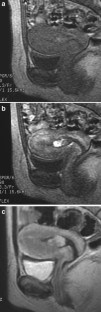

The endometrial cavity may demonstrate various imaging manifestations such as normal, reactive, inflammatory, and benign and malignant neoplasms. We evaluated usual and unusual magnetic resonance imaging (MRI) findings of the uterine endometrial cavity, and described the diagnostic clues to differential diagnoses. Surgically proven pathologies of the uterine endometrial cavity were evaluated retrospectively with pathologic correlation. The pathologies included benign endometrial neoplasms such as endometrial hyperplasia and polyp, malignant endometrial neoplasms such as endometrial carcinoma and carcinosarcoma, endometrial–myometrial neoplasm such as endometrial stromal sarcoma, pregnancy-related lesions in the endometrial cavity such as gestational trophoblastic diseases (hydatidiform mole, invasive mole and choriocarcinoma) and placental polyp, myometrial lesions simulating endometrial lesions such as submucosal leiomyoma and some adenomyosis, endometrial neoplasms simulating myometrial lesions such as adenomyomatous polyp and endometrial lesions arising in the hemicavity of a septate/bicornate uterus, and fluid collections in the uterine cavity (hydro/hemato/pyometra). It is important to recognize various imaging findings in these diseases, in order to make a correct preoperative diagnosis.